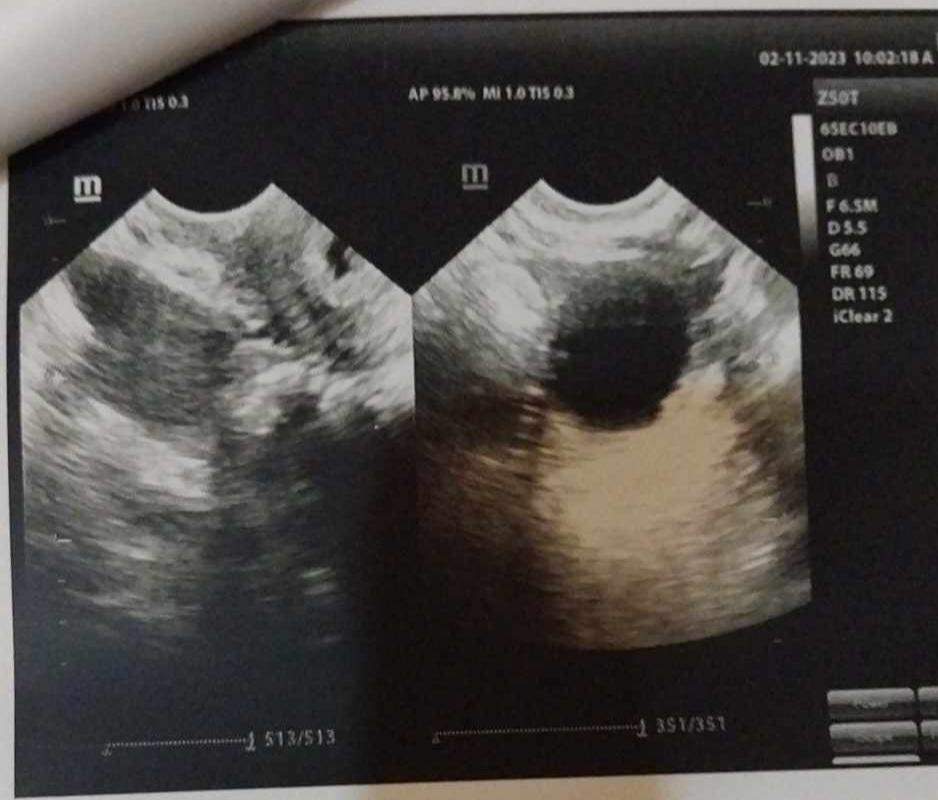

قراءة اشعة سونار علي الرحم